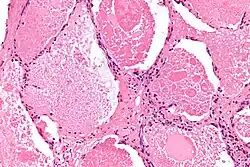

| Micrograph of pulmonary alveolar proteinosis, showing the characteristic airspace filling with focally dense globs referred to as chatter or dense bodies. H&E stain. | |

Lung washings or tissue for histopathologic analysis are most commonly obtained using bronchoalveolar lavage and/or lung biopsy.[13] Characteristic biopsy findings show filling of the alveoli (and sometimes terminal bronchioles) with an amorphous eosinophilic material, which stains strongly positive on PAS stain and the PAS diastase stain. The surrounding alveoli and pulmonary interstitium remain relatively normal.[14] Electron microscopy of the sample, although not typically performed due to impracticality, shows lamellated bodies representing surfactant.[15] An alternative diagnosis with similar histomorphologic findings is Pneumocystis jirovecii pneumonia.[15]

Lung washings characteristically yield a fluid which is "milky"composition. Under the microscope, samples show 20-50 micrometer PAS-positive globules on a background of finely granular or amorphous PAS-positive material. There is typically a low numbers of macrophages and inflammatory cells (although this is variable).[14][15]